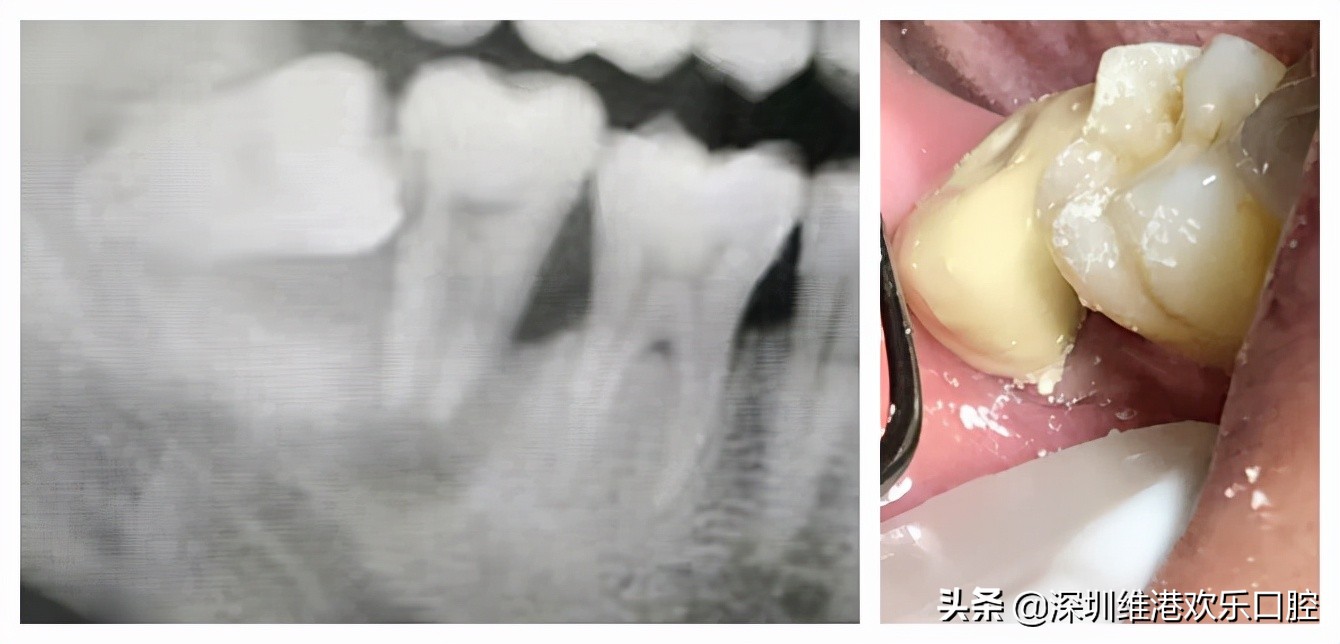

高主任:我对於微创牙科学的理解,在治疗过程中儘量减少对牙体或者伤口的损伤之外,能保留的牙齿都尽量保留。去年有一位34的男士,阻生智齿因为没有及时拔除,导致7號牙严重松动,去了其他牙科都建议拔除,后来他经家人介绍到我就职的牙科,经过检查之后还是儘量帮他保留,拔智齿时,先把这个极松的7號牙和6號牙用玻璃离子粘结稳,先將7牙磨低磨小开髓置Fc棉暂封,然后拔掉智齿,等7牙慢慢恢復。现在7號牙通过冠修復之后成功保留了!